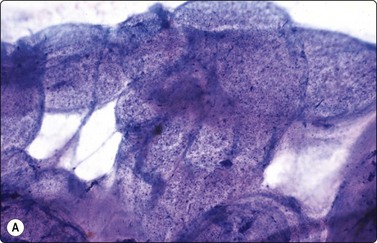

Seminoma (Figs 13.30 and 13.31)14,50,57-63,65,66

Fig. 13.30 Seminoma

(A) Dispersed cells with large pale nuclei and poorly defined cytoplasm; note ‘tigroid’ background, smudged nuclei and small lymphocytes (MGG, HP); (B) Dispersed cells; moderately pleomorphic vesicular nuclei; single or multiple prominent nucleoli; many scattered lymphocytes (Pap, HP).

Criteria for diagnosis

Cell-rich smears,

Dispersed cells, little tendency to clustering,

Highly fragile cytoplasm and nuclei (’tigroid background’ (TB) and nuclear trailing),

Large rounded vesicular nuclei; distinct nucleoli, smaller than in embryonal carcinoma,

Irregular chromatin with some clearing,

Abundant fragile, pale/clear cytoplasm; some marginal vacuoles (punched-out vacuoles),

Lymphocytes, plasma cells,

Tangled chromatin threads (seminoma cells and lymphocytes),

Some epithelioid histiocytes, epithelioid granulomas (variable),

Striking contrast in size between seminoma cells and the background of lymphocytes and plasma cells.

Immunocytochemistry: cells positive for PLAP, c-kit (CD117) and OCT 3/4, and negative for CD30, AE1/AE3, and CK7, CK8, CK18 and CK19, although focal pancytokeratin-positive cells may be seen.

Seminoma is a highly cellular neoplasm of poorly cohesive cells and little stroma. The presence of a lace-like tigroid background (TB), and the high cellularity including lymphocytes account for the intense navy-blue color of the smears. This may suggest the diagnosis even before microscopic study. Comments about the origin of TB and the distinction from ‘lymphoglandular bodies’ have been made elsewhere.60 TB may go unnoticed in Pap-stained smears, but is more conspicuous in DQ smears (Fig. 13.30). A diagnosis of seminoma should not be based solely on the presence of TB or TB-like material. We have observed TB-like material also in aspirates of embryonal carcinoma. The contrary is also true: seminoma should not be ruled out simply because the pathologist is unable to identify TB.14 Large seminomas may show prominent necrosis. Necrosis is a major cause of false negatives in testicular FNA.59 Tumor giant cells or syncytiotrophoblastic cells may be seen in aspirates of seminoma, but can also be found in embryonal carcinoma, mixed TGCT and in trophoblastic tumors.

The plasmatic membrane is well-defined in seminoma, but it is difficult to see in embryonal carcinoma. When lymphocytes, plasma cells, histiocytes and epithelioid granulomas are abundant and seminoma cells scarce, a diagnosis of granulomatous orchitis may be entertained: the absence of spermatozoids and of the germinal line suggest a seminoma.60

Chromatin trailing may be prominent, particularly if the sample was smeared vigorously. This artifact has no diagnostic value in itself, since it may occur also in embryonal carcinoma, yolk sac tumors, lymphomas and acute orchitis. When the smear is dominated by this artifact, and there are no acute inflammatory cells and no spermatogenesis, the pathologist must search carefully for preserved diagnostic cells. In this situation, a tentative diagnosis of seminoma may be made.14

Lymphocytes, plasma cells and even ‘lymphoglandular bodies’ may be prominent in smears of seminoma and may lead to an erroneous diagnosis of lymphoma. Lymphoblasts may also be mistaken for seminoma cells.

Familiarity with the cytology of testicular seminoma helps in the recognition of extragonadal seminoma and metastatic seminomas (Fig. 13.31). Immunostaining may be of help in doubtful cases.69